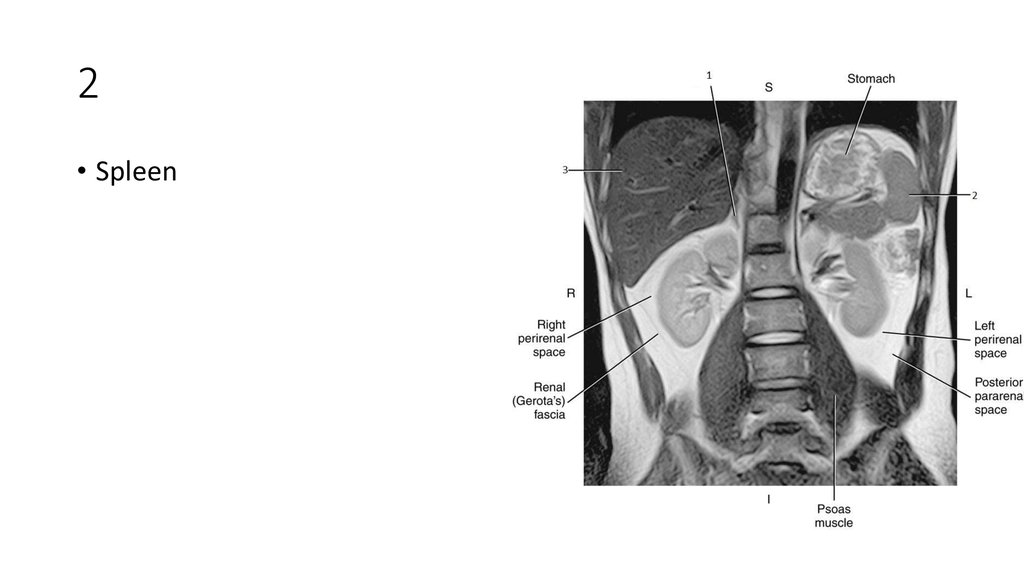

12. 2

13. 2

• Spleen